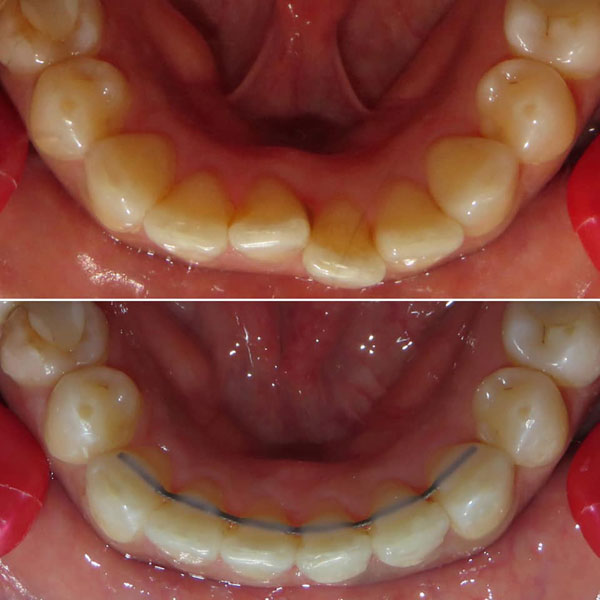

Permanent retention to hold the corrections |